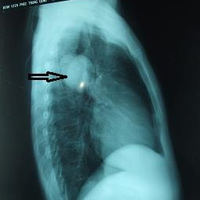

Túi ấu trùng có hình dạng như mẫu trứng, bên trong có chứa sán con

Bác sĩ thực hiện ca phẫu thuật cho biết “Nhìn nó giống như một túi trứng nhỏ, bên trong túi ấu trùng là sán con.”